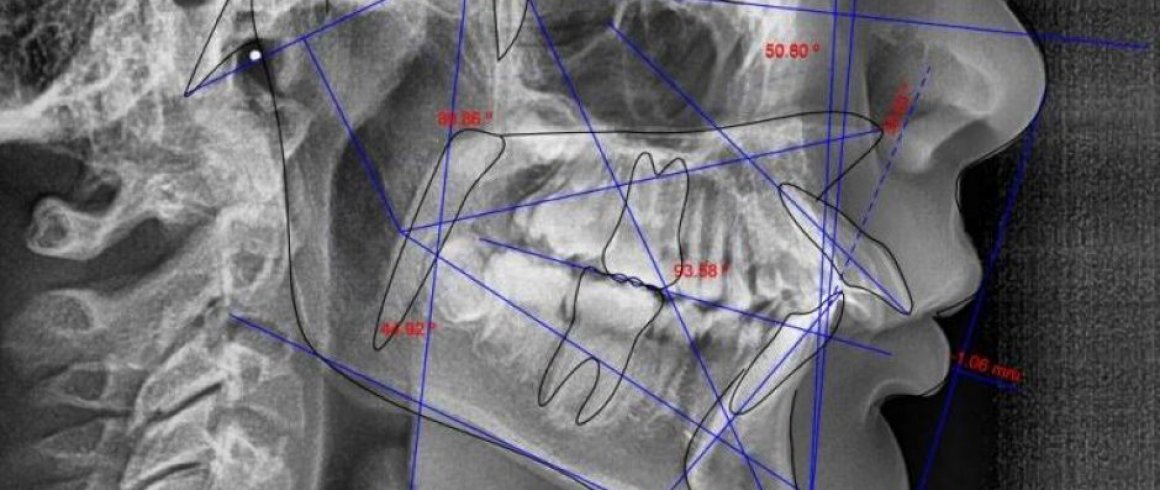

- Lateral (Cefalometrica)

- Análisis Cefalométrico Lateral